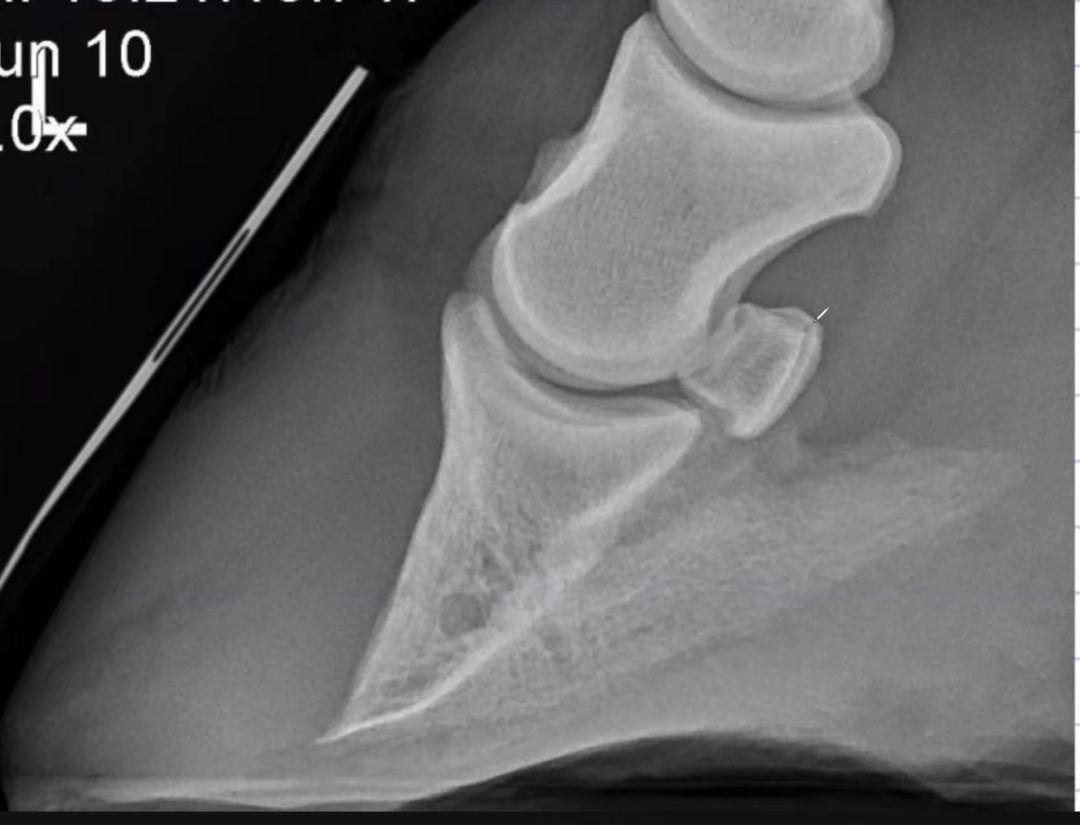

除了情景问题,还会有图片和图表分析题目。图片有时是X光图,有时是一张动物相关的图。面试中我得到的题目是一张养鸡场的图,我不只说到了鸡的健康,还提到这如何与人类和环境关联起来,也就是 One Health的概念——兽医不只要治疗动物,他们还要负责食品安全、动物保护、以及科研等。所以在面试中你一定要表现出对兽医学的理解,表示自己并没有拘泥于宠物诊所这一种职业选择,而是看到了兽医学未来的可能性。

(图片为面试准备过程中学习用X光图)